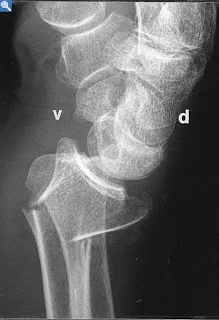

Galeazzi Fracture/ Dislocation

Fracture of the radius with dislocation of the distal radio-ulnar joint

“Fracture of necessity”

- Necessitates surgery

“Fracture of necessity”:

- Plating of radius

- Reduction of distal radio-ulnar joint (+/- Fixation)